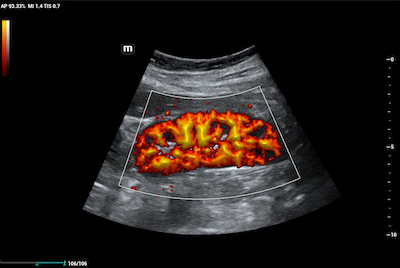

- Ultra Micro Angiography (UMA) is an innovative method of visualizing low-velocity micro-vascular flow states. UMA compensates for the limitations of traditional flow modes in detecting slow flow. It allows for visualization of the supply vessels surrounding diseased tissues, further enhancing diagnostic capabilities for lesion detection and characterization.

- Color UMA – UMA with a traditional color map overlay for improved sensitivity

- Power UMA – UMA with Power Doppler sensitivity, also available in bidirectional mode

- Subtraction UMA – UMA combined with tissue subtraction for enhanced evaluation of vessels separate from grayscale imaging

Subtraction Ultra Micro Angiography of Renal Profusion